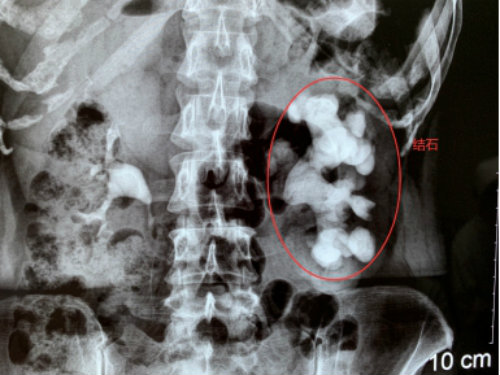

2019年11月18日,孝感一女子左腎里的結(jié)石長(zhǎng)成“精”,長(zhǎng)達(dá)12公分,形似一個(gè)“老生姜”,慕名到武漢京都結(jié)石醫(yī)院保腎取石,康復(fù)之際,被武漢多家媒體爭(zhēng)相報(bào)道后,一時(shí)間成了病房里的網(wǎng)紅。

18年前,魯女士在孝感當(dāng)?shù)蒯t(yī)院查出左腎小結(jié)石。因?yàn)閺膩?lái)沒(méi)癥狀,她就沒(méi)管過(guò)。最近兩年,她又因長(zhǎng)期右腰疼痛被查出腰椎間盤(pán)突出。上周,在準(zhǔn)備接受腰椎病治療的時(shí)候,CT結(jié)果提示她的左腎被結(jié)石撐滿,醫(yī)生建議她趕緊手術(shù),否則腎可能不保。

內(nèi)心十分害怕的魯女士專程趕到親戚推薦的武漢京都結(jié)石醫(yī)院,醫(yī)生指出,說(shuō)所患的是臨床上比較罕見(jiàn)的巨大鹿角形結(jié)石,處理起來(lái)很棘手。幸運(yùn)的是,她的雙鏡聯(lián)合微創(chuàng)保腎取石手術(shù)很成功,左腎里的“姜王”結(jié)石在一期手術(shù)中得到了有效處理,術(shù)后也恢復(fù)得不錯(cuò)。

為了有效預(yù)防結(jié)石再生,醫(yī)生對(duì)魯女士的結(jié)石做了成分檢測(cè),提示為感染性結(jié)石。醫(yī)生提醒,該類結(jié)石的生長(zhǎng)速度極快,手術(shù)取石后遵醫(yī)囑采取有效的藥物控制也是十分必要的。